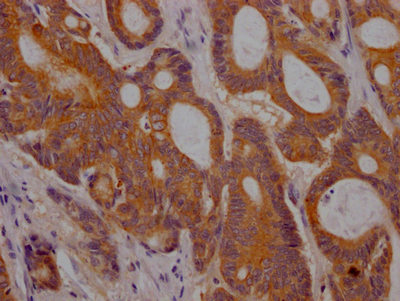

IHC image of CSB-RA280380A0HU diluted at 1:100 and staining in paraffin-embedded human colon cancer performed on a Leica BondTM system. After dewaxing and hydration, antigen retrieval was mediated by high pressure in a citrate buffer (pH 6.0). Section was blocked with 10% normal goat serum 30min at RT. Then primary antibody (1% BSA) was incubated at 4℃ overnight. The primary is detected by a Goat anti-rabbit IgG polymer labeled by HRP and visualized using 0.05% DAB.